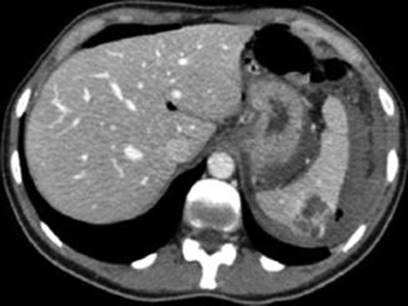

9.1.5.5 Abdominal CT Scan

Native abdominal MSCT scan especially with i.v. contrast can define SAA with or without rupture preoperatively but is almost never used in pregnant patients, as well as angiography. Abdominal CT scan is used when MRI is not available in emergency settings (Fig. 9.4).

Fig. 9.4

An oblique sagittal reformatted CT scan image showing traumatic splenic laceration (right arrow) and the 26-week fetus (left arrow) [45]